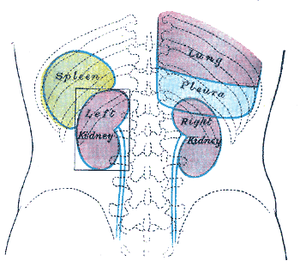

Transverse section of the spleen, showing the trabecular tissue and the splenic vein and its tributaries. Back of lumbar region, showing surface markings for kidneys, ureters, and spleen.

Back of lumbar region, showing surface markings for kidneys, ureters, and spleen. Side of thorax, showing surface markings for bones, lungs (purple), pleura (blue), and spleen (green).